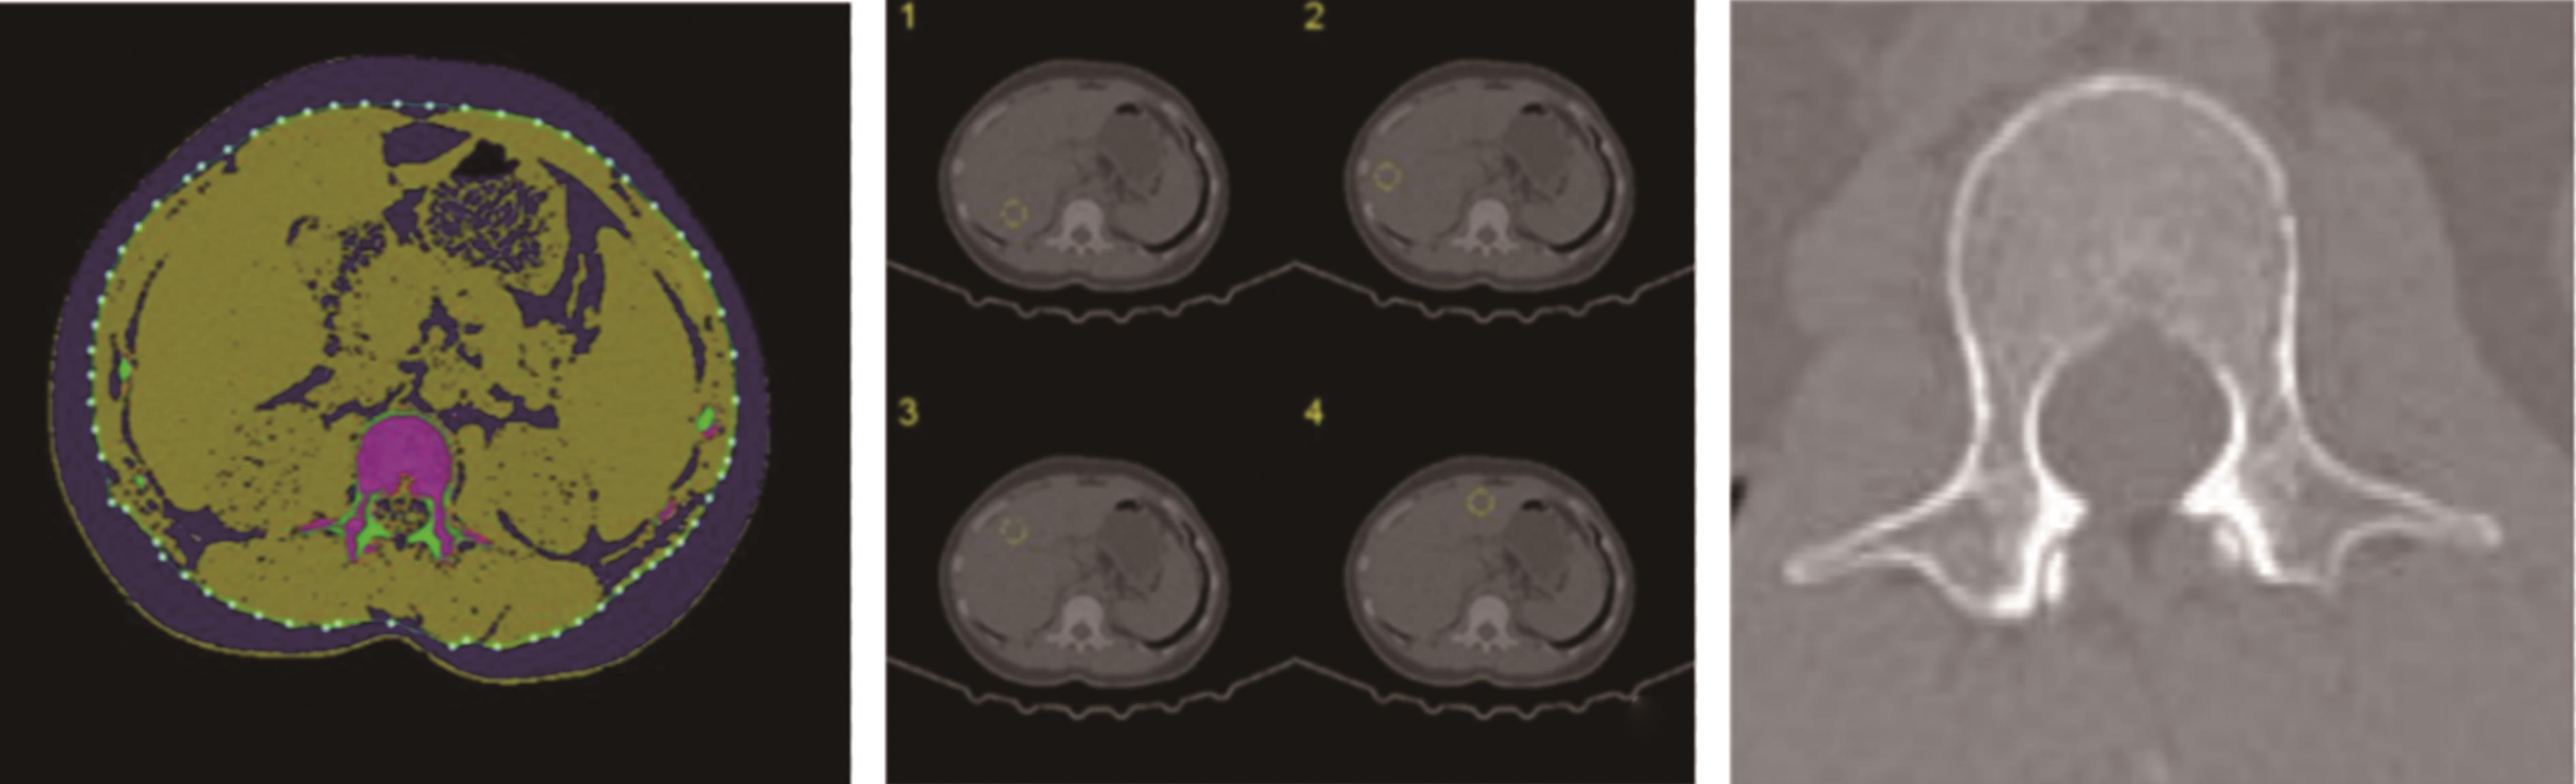

摘要:目的 通过转录组测序(RNA sequencing,RNA-Seq)和TMT蛋白质组学技术,筛选差异表达的基因及蛋白,探讨脊髓损伤后复杂的病理机制。方法 50只雌性C57BL/6小鼠随机分为假手术组、模型组,每组25只。采用钳夹法在腰1处制备小鼠脊髓损伤模型,14 d后进行取材。采用后肢运动功能评分(basso mouse scale,BMS)评估小鼠后肢运动功能变化;HE染色法观察脊髓损伤区病理形态学变化;RNA-Seq技术筛选差异基因;TMT蛋白组学分析筛选差异蛋白;结合2种测序技术筛选变化趋势吻合的mRNA和蛋白并进行生物信息学分析。结果 与假手术组相比,模型组中BMS评分明显降低(P<0.05);HE染色显示脊髓损伤区域结构疏松紊乱,出现空洞,细胞核固缩,炎性浸润严重,神经元坏死;RNA-Seq共筛选出565个差异mRNA,其中545个上调,20个下调,TMT蛋白组学共筛选出339个差异蛋白,其中278个上调,61个下调;2种测序的聚类热图显示2组样本的表达模式差异大;韦恩图分析获得83个趋势上调的mRNA或蛋白;蛋白互作(protein-protein interaction,PPI)网络分析获得11个核心靶点;GO富集分析显示分子功能或生物过程主要在免疫应答、溶酶体途径、细菌反应、液泡裂解等方面;KEGG富集通路主要在结核病变、溶酶体、吞噬小体途径等通路。结论 本研究筛选出的11个mRNA或蛋白可能是调控脊髓损伤病理过程的核心靶点,病理机制可能与免疫应答途径、溶酶体和吞噬小体等通路密切相关。